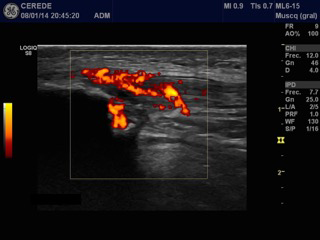

Structural findings of collagen degeneration and angiofibroblastic neoplasia have been well described and are now referred to as "neovascular tendinosis." The presence of neovascularization has been theorized to cause pain in patients with tendinopathy.2 Recent studies have examined the role of neo-vessels and neo-innervations on chronic tendon pain and dysfunction, and interventions targeting this process have reported favorable outcomes in RPT (Figure 1-4).3

Figure 2 Patellar tendinopathy treatment using EPI® device (EPI Advanced S.L. Barcelona, Spain)

Ultrasound-guided Intratissue percutaneous electrolysis (EPI®) treatment is the application of a direct current (DC) whose catodic flow is transferred to the area of the degenerative tendon using an acupuncture needle.4 This accumulated electrical charge (AEC) in the degenerative tissue will produce the activation of the molecular, cellular and biological processes necessary to restore the regeneration mechanisms of the tendon. In recent studies it has been demonstrated that EPI® technique is effective in tendinopathy and sport muscular injuries.5–7